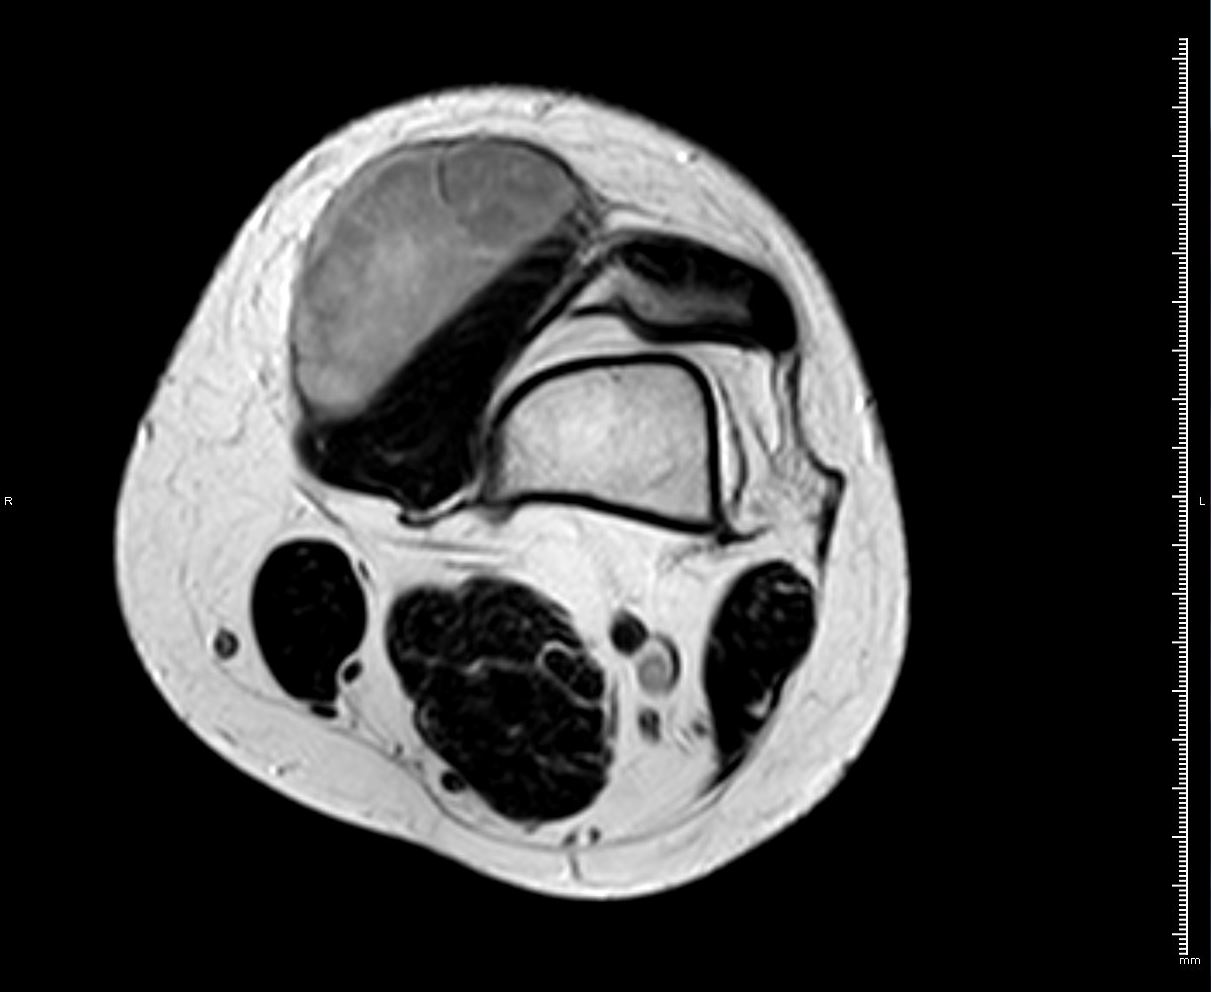

RM T1 con supresión grasa y contraste IV

HALLAZGOS RADIOLÓGICOS